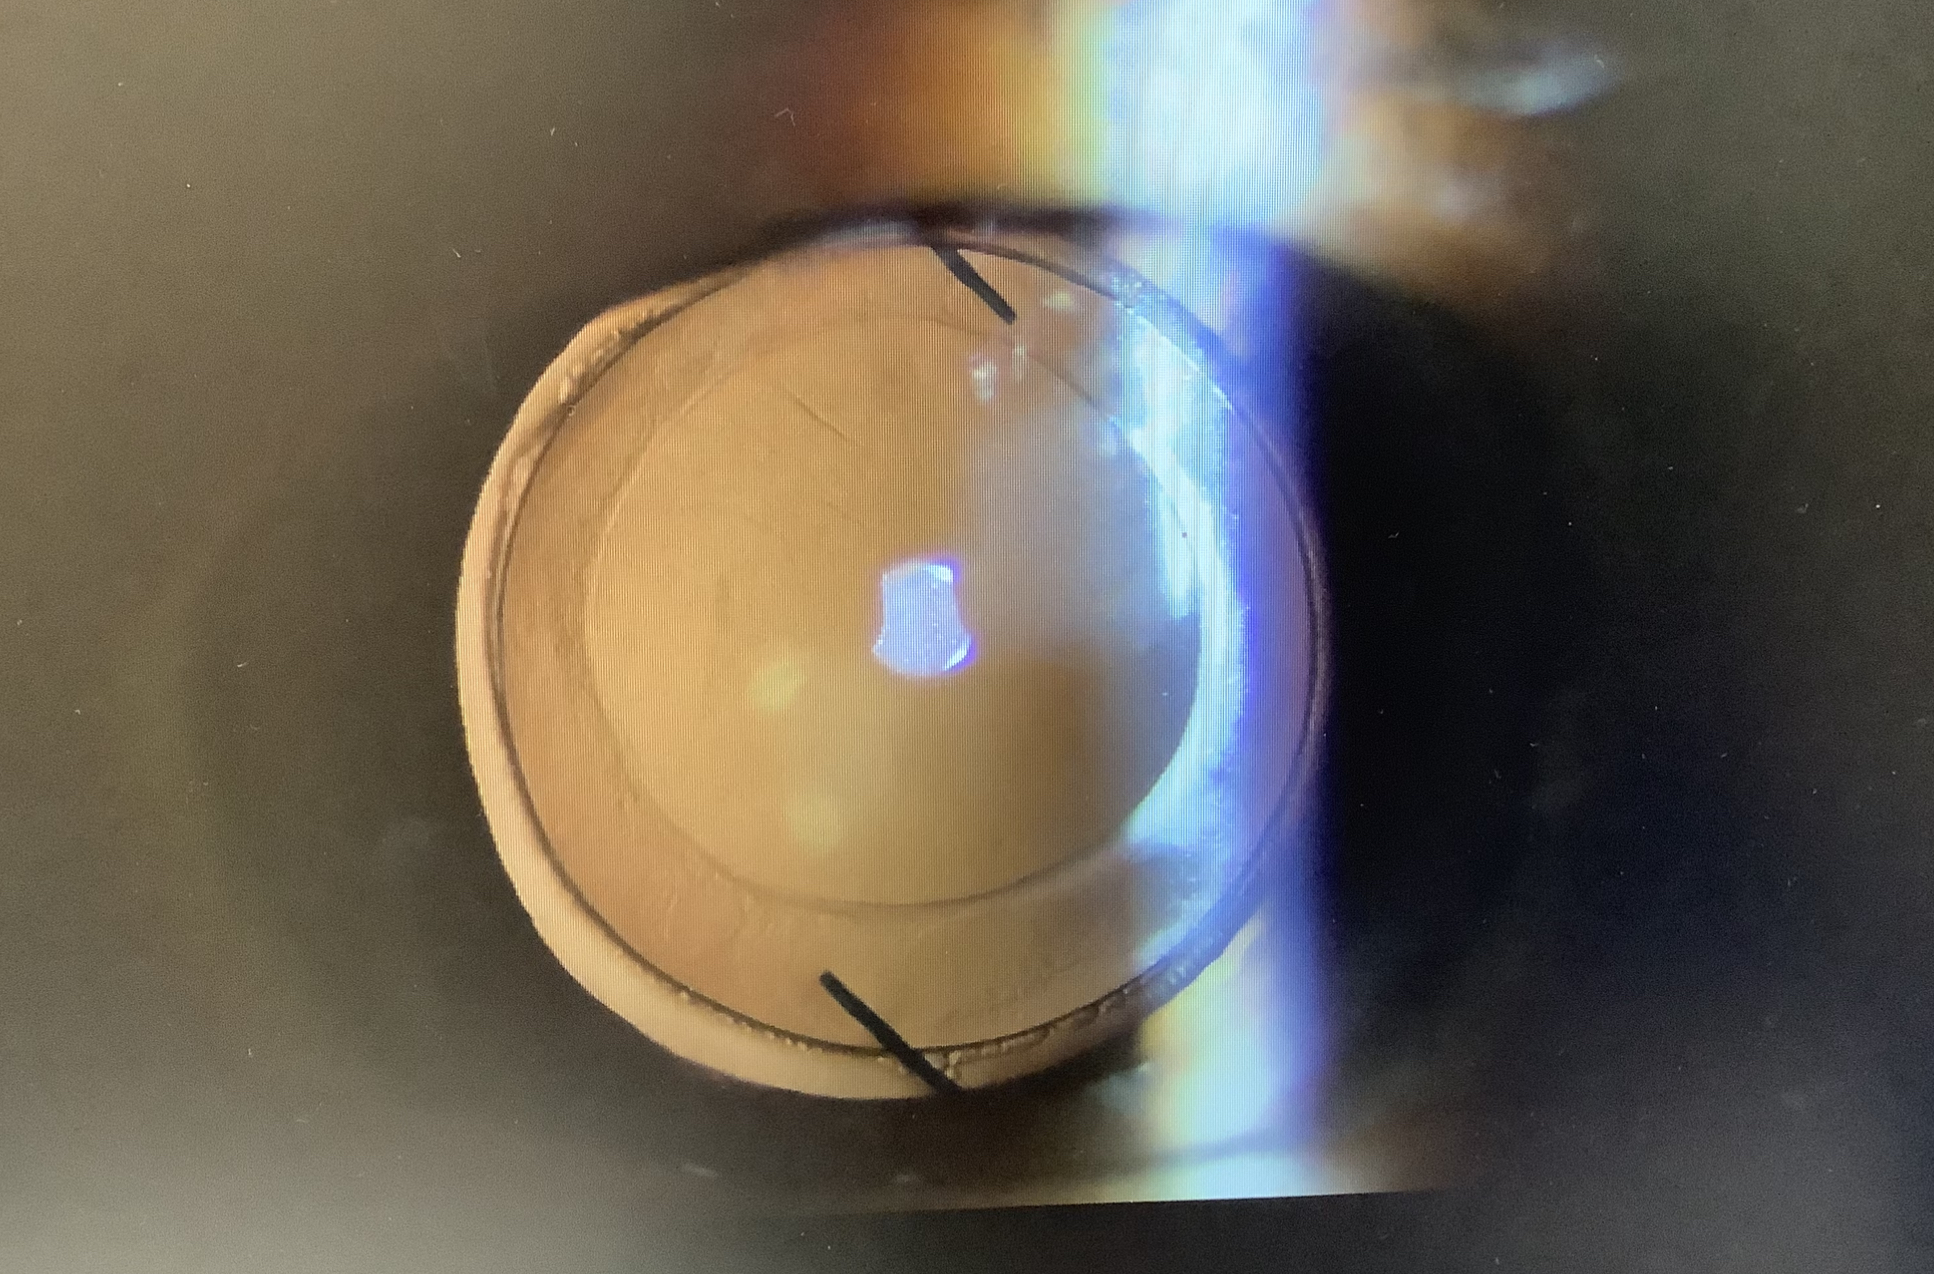

今日、眼内レンズ交換の手術の申し込みをいただいた60代の女性の方は、4月に右眼の白内障の手術を受けたところ、+2Dの遠視になり、見えにくくて困ってしまい、当院へ相談にいらっしゃいました。普通の眼でこれだけ計算がズレることは滅多にないのですが、この方の場合、LASIKを2度行い、かなり薄くなった眼だったため、度数がズレてしまったようです。遠視というと、遠くがよく見える眼と思われるかもしれませんが、遠視は遠くが見る眼のことではなく、網膜表面よりも奥側に焦点が結ばれる眼の状態で、ピントを合わせる調節力があれば、その焦点を網膜表面に作ることで遠方を見ることができるのですが、眼内レンズの眼では調節力は基本的に働かないので、眼の奥にできた焦点はそのままになってしまいます。そのため、遠方も近方も見えにくい不便な眼になってしまい、+2Dも遠視ズレすると、見え方としてはかなり辛い状況と思われました。なので、単純にレンズの度数がよくないため、シンプルに眼内レンズの入れ換えを行うのがよいのではと提案させていただきました。

LASIKでかなり薄い角膜ではありますが、今、入っているレンズの度数から逆算して、新たなレンズの度数を選んであげれば、今よりは合った度数に十分できるかなと思うので、なんとか見やすい眼にできるように頑張りたいと思います。